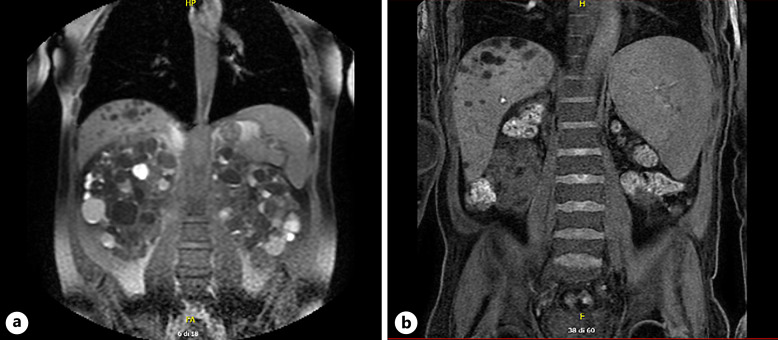

Case presentation: We present a case of hepatic fibrosis with splenomegaly and severe pancytopenia as a tardive complication after bilateral nephrectomy in 47-year-old ADPKD patient.

Conclusion: This finding underscores the critical significance of meticulously examining the anatomical relationship between polycystic kidneys and the liver before performing nephrectomy. Additionally, it highlights the importance of assessing liver involvement and associated complications. By integrating liver assessment into the criteria, we can significantly enhance patient care and improve the overall management of ADPKD before kidney transplantation.